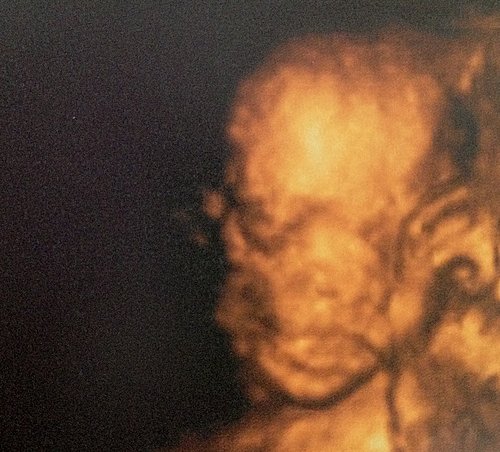

跟住我哋又問靳醫生,可唔可比阿 b 個樣我哋睇,靳醫生當然話無問題啦~

呢次阿 B 好合作,等靳醫生幫佢影到幾張都算清楚的相比我哋~